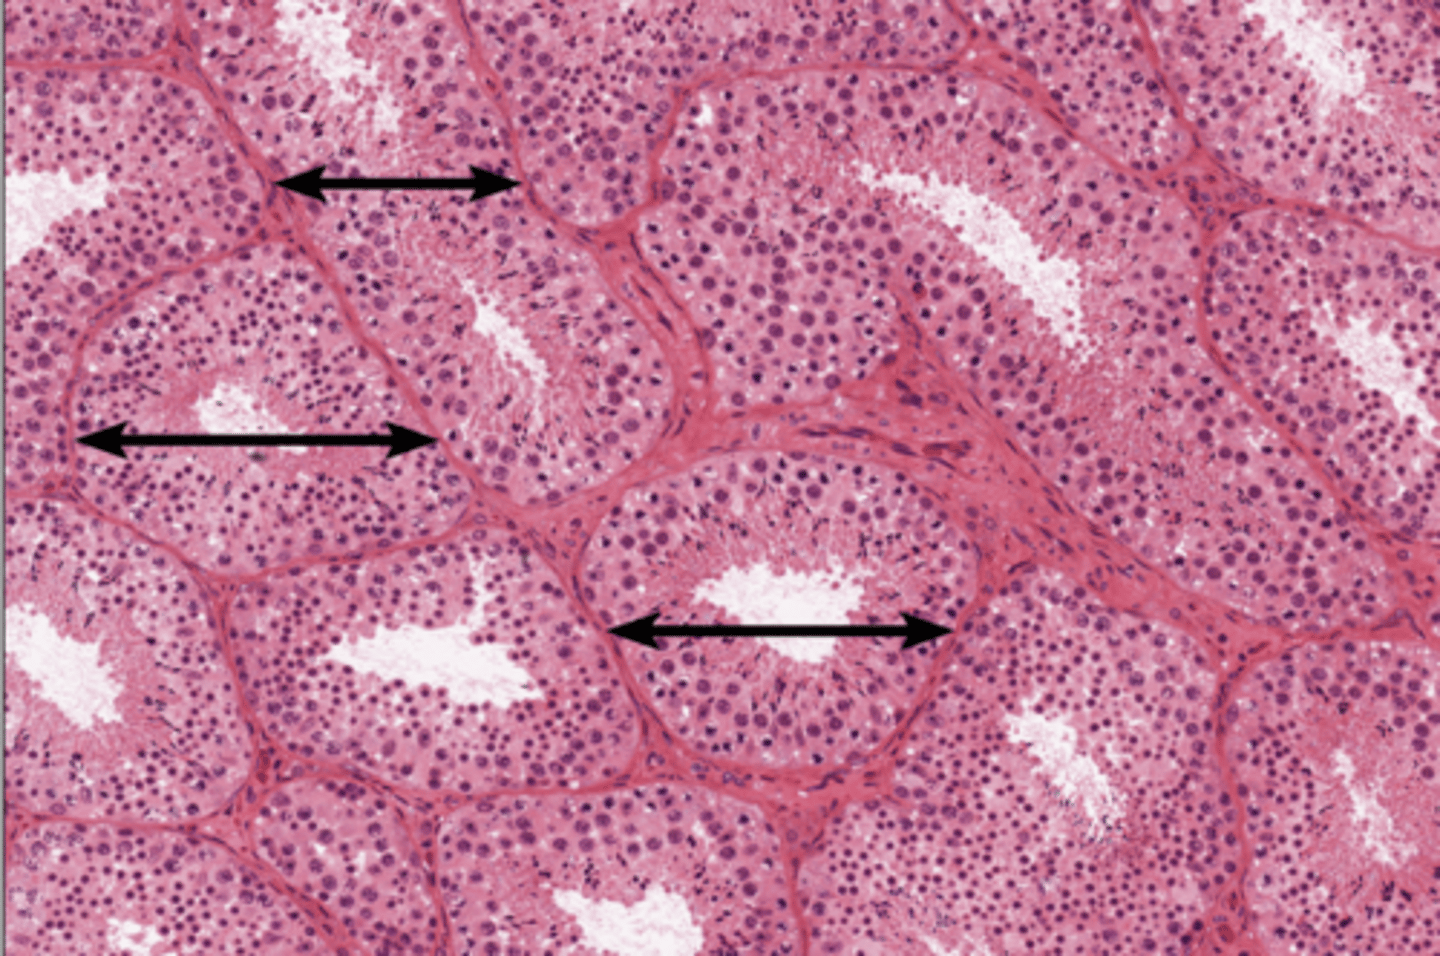

Seminiferous tubules

Seminiferous tubules

Seminiferous tubules

Leydig cell

Leydig cell

Lobule

Spermatogenesis

Spermatogenesis

Spermatogonia

Primary spermatocyte

Spermatogonia

Spermatid (early)

Primary spermatocyte

Spermatid (late)

Spermatid (early)

Spermatozoon

Spermatid (late)

Spermatozoa